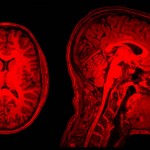

30 Januari 2010: Als proefpersoon in de MRI scan

8 maart 2010: Ontvangst hersenscans

Daar stonden dan eindelijk mijn hersenscans ingepakt in een pakketje in mijn postvak-in! Ja zeker 3D beelden! Na snel wat programma’s als MRICron en MRIcro te installeren kon ik al snel door mijn brein heen scrollen. Van craniaal naar caudaal, dorsaal naar ventraal en van lateraal naar lateraal. MRIcron hield me nog wel even zoet.